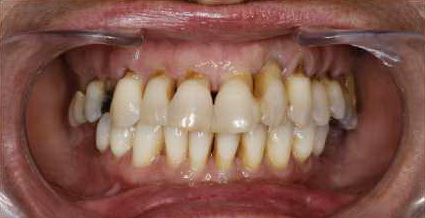

Oral Care is a company with almost no redundant staff

You can find that, except for a few rare cases, missing teeth almost always need to be filled. If the oral cavity is likened to a company, except for wisdom teeth, there are no redundant employees in this company. Every tooth is an important employee with important responsibilities. Each tooth has its own function and matching structure with the adjacent teeth. As long as there is one tooth, the tooth will be in good condition. When employees get injured or leave, it increases the burden on other employees and affects company operations. The same is true for teeth, which are closely related. Losing a tooth is not as simple as just that tooth is missing.Procrastination does not solve problems, it only makes them more complicated.Many patients choose to ignore missing teeth, but delay will not solve the problem. When these patients come back for treatment due to new problems caused by missing teeth, they find that the original missing tooth still needs to be treated. Moreover, because the problem has been delayed for too long, the gums may have eceded and bone filling may be required, and the adjacent teeth may be crooked. It may even fall like dominoes.In short,there are many problems to deal with. This increases the difficulty of reconstruction, and of course the time and costof treatment will also increase.

The oral cavity is like a company that relies on cooperation. In this company, except for wisdom teeth, every tooth has an important task. They are interdependent and influence each other. The absence of any one of them will lead to dysfunction.

When teeth are displaced, their arrangement becomes uneven, creating many blind spots for cleaning, which harbor dirt and cause periodontal disease and new cavities.

When a tooth is missing, the chewing task that was originally borne by this tooth will be transferred to other teeth, accelerating the wear of the enamel of other healthy teeth and even causing sensitivity problems.